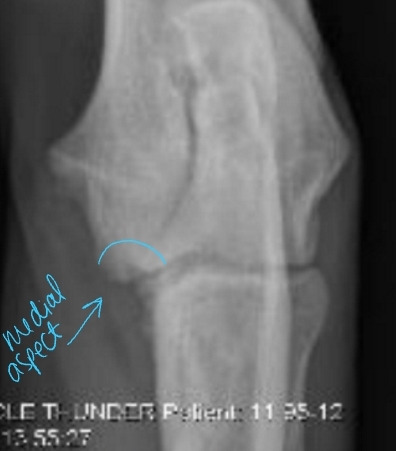

Medial Compartment and Coronoid Disease

Growing/developmental disease, Bilateral

Et: Growth incongruency radius/ulna, abnormal joint stress, pressure on medial coronoid of ulna

Sig: Large breed dogs, Labs, Bernese Mountain Dog, Male > Female, 6-18 months

Cs: OA, Lameness with ambulation, Decreased ROM of elbow joint, Pain(PE/palpation), Minimal joint effusion, Muscle atrophy

Dt: Lateral, AP, flexed, Crlat-oblique

Rads: Osteophytes(back of elbow), Effusion, Subtrochlear sclerosis, Joint incongruity

CT: Most sensitive

Tx: Rx: Management of OA

Sx: gold standard

Medial arthrotomy:

Cons: Limited view, high postoperative morbidity

Arthroscopy (#1): gold standard

Pro: Min invasive, good view

Cons: higher cost, learning curve